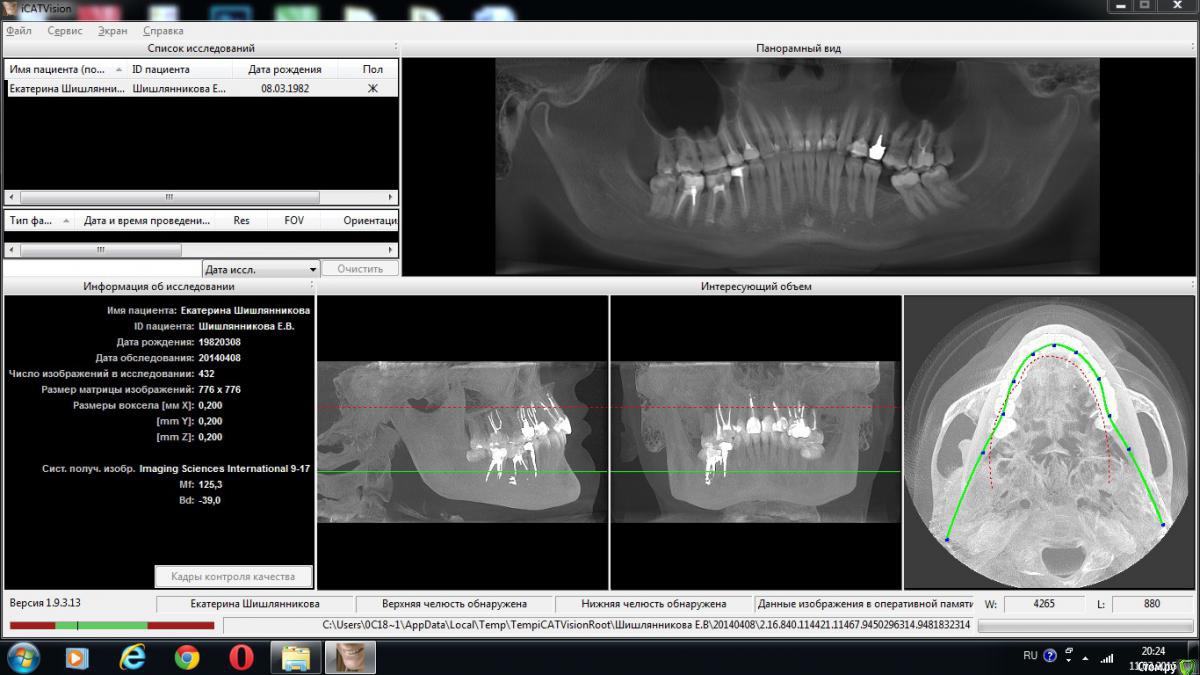

Екатерина Ш Опубликовано 13 марта, 2015 Поделиться Опубликовано 13 марта, 2015 (изменено) Здравствуйте!Зуб номер 46, лечен резорцин-формалиновым методом лет 15-20 назад.фото, принтскрин КТ и просто рентген https://cloud.mail.ru/public/88d029743dfe/%D0%B7%D1%83%D0%B1%D1%8B Красный. Очень чувствительный - шейка оголена.В последнее время начал ныть, особенно по ночам, прям чувствую, что ноет в кости. Говорят киста. И только удалять. Ибо даже если возможно будет пройти каналы, то он треснет и одеть на него коронку не представляется возможным(Ваше мнение? Спасибо заранее Изменено 13 марта, 2015 пользователем Екатерина Ш Ссылка на комментарий

shishok Опубликовано 13 марта, 2015 Поделиться Опубликовано 13 марта, 2015 В последнее время начал ныть, особенно по ночам,На всякий случай проверьте и 48 на наличие скрытой полости(и возможного пульпита). Ссылка на комментарий